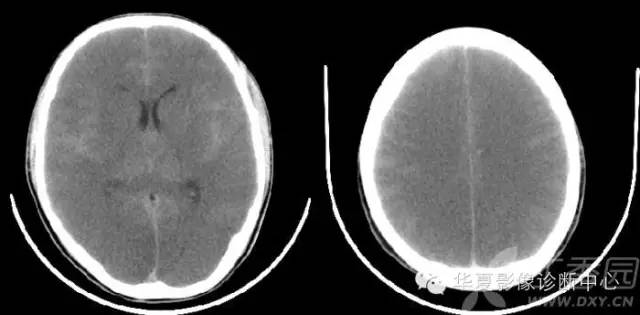

反转征

儿童弥漫性脑白质和灰质的密度减低、伴有灰白质界限不清或消失,或灰白质密度反转,而丘脑、脑干和小脑密度相对增高。根据“反转征”出现时间分急性和慢性2期。急性指当时CT扫描即有“反转征”,慢性为弥漫性脑萎缩/脑软化伴“反转征”。

基底节和丘脑损害所发生的密度增高目前有几种认识:国内学者认为系缺氧后上述区域发生大理石样变性所致,表现为神经元的丧失、星形细胞胶样变性及髓鞘过度形成,尤其壳核背外侧与丘脑腹外侧髓鞘化最活跃,需氧量最高,代谢旺盛,对缺氧缺血敏感,因此受累也最为严重。有的则认为是严重缺血后1~2周新生毛细血管网的大量增加或与大脑的白质深部髓质静脉扩张淤血有关,甚至有人认为不是密度增高,而是正常脑组织密度。这种密度增高是相对的,虽然在急性期脑中央区域的密度增高个体间存在一定的密度差异,但本组从未见有像脑血管破裂出血那样的高密度,CT值多在22 HU左右,因此这种密度增高是相对的。“反转征”的分期,急性期应以生后当时CT扫描结果为准。一般来说,生后3 天多以脑水肿为主,其后为脑实质缺氧缺血性损害,所以生后5~10 天扫描较为可靠。慢性期以生后3~8周为妥,此期已出现明显脑软化、脑萎缩,脑实质密度明显低于急性期。急性“反转征”的患儿需要呼吸支持和重症监护,延误治疗者可转变为慢性“反转征”,其密度变化更具有特征性。有人认为重症病人在3个月时即可发生脑软化和脑萎缩,发生率约占HIE病例的20%。与此同时,丘脑与脑干的密度增高较急性期更加显著,如同“增强”一样,CT值22~26 HU,丘脑形态轮廓勾画清楚,犹如雪山的“山丘”,出现这种明显反差的影像学表现可能与脑软化的低密度衬托有关,若不仔细的观察和测量CT值易误为脑出血。“反转征”主要发生在重度HIE病例中,因此“反转征”可视为重度HIE少见而重要的征象,可把它作为HIE诊断及分级和评价预后的重要依据。CT“反转征”是新生儿重度缺氧缺血性脑损伤的一种重要CT征象,但并非特异性,也可以在某些疾病中如外伤(虐待伤)、病毒性脑炎等出现。特别应注意慢性“反转征”与HIE的并发症鉴别。众所周知,HIE常见并发症为外部性脑积水和局限性脑软化灶和脑萎缩,前者不存在鉴别问题,后者CT上脑软化灶多发生在顶枕叶或双侧脑室旁白质内,多为局限性,而慢性“反转征”则表现为半球弥漫性低密度区,同时基底节及丘脑等脑中央区域密度增高明显,表现特殊,这点对鉴别诊断有相当重要的价值。因此,重度窒息儿大脑灰白质密度弥漫性减低伴灰白质界限消失或密度反转以及基底节、丘脑、脑干和小脑密度相对增高是重度HIE的特征性CT表现,是诊断急、慢性CT“反转征”的重要依据。急性期脑室受压变窄和慢性期脑室扩大主要与脑水肿和脑软化/脑萎缩有关。“反转征”一旦出现,高度提示脑组织有不可逆性脑损伤存在,预后大多不良,即使存活也将发生脑瘫或智力障碍等后遗症。